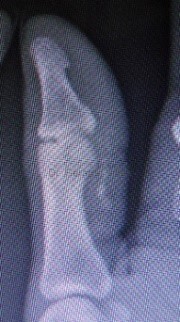

Estudios médicos que se pueden solicitar según el caso clínico son; Análisis de sangre (recuento de glóbulos blancos, marcadores inflamatorios etc.) Radiografías, Ecografía y la Resonancia Magnética pueden ayudar a distinguir las causas infecciosas de las no infecciosas.